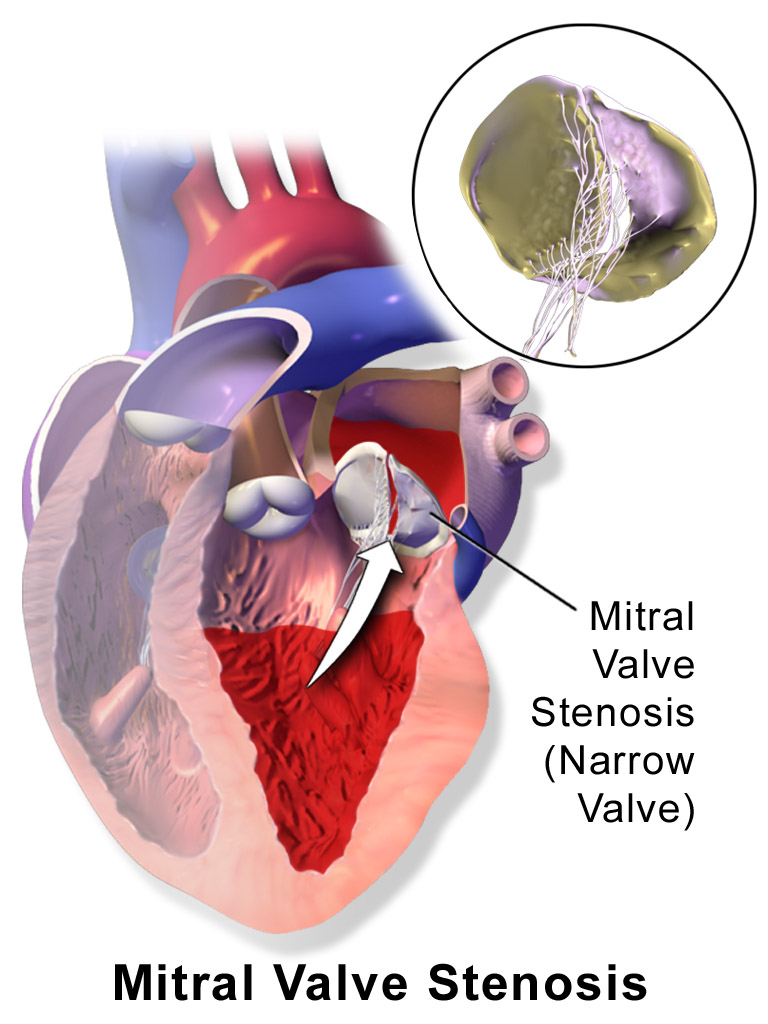

Mitral Stenosis

The narrowing of the mitral valve orifice is known as mitral stenosis.

Mitral stenosis is associated with persistent rheumatic valve disease.

Clinical findings of mitral stenosis include:

- An opening snap followed by a diastolic rumbling

- Volume overload that causes the left atrium to enlarge

- Pulmonary congestion with edema and alveolar hemorrhage

- Pulmonary hypertension

- Possibly right-sided heart failure

Mitral stenosis may cause atrial fibrillation with associated risk for mural thrombi.